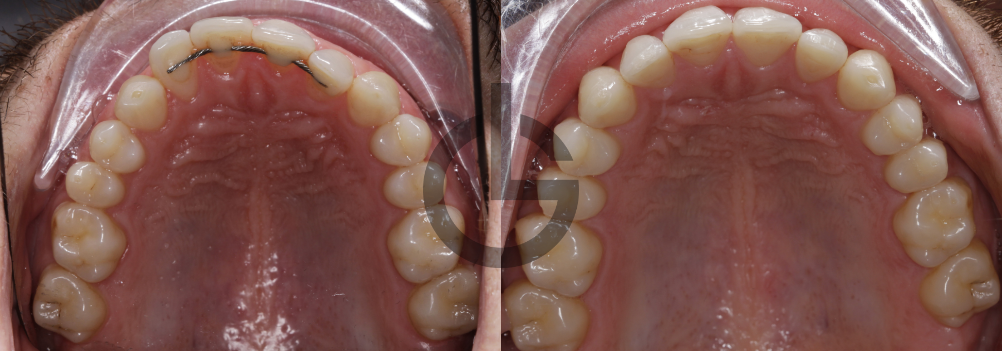

el paciente presentaba una mordida abierta anterior severa provocada principalmente por una deglución atípica. Esta situación impedía un correcto engranaje posterior, generando complicaciones en la masticación y afectando su calidad de vida. Además, se identificó una estructura facial con perfil recto normofacial, pero con una marcada tendencia hacia una clase II esquelética y planos oclusales divergentes, factores que sumaban complejidad al tratamiento.

Evaluación del progreso tras primera etapa

Al concluir esta primera fase, se realizó un análisis exhaustivo para evaluar la efectividad de los alineadores invisibles. Esta etapa fue crítica para determinar si sería necesaria una intervención adicional con microtornillos.

Segunda fase: intervención precisa con microtornillos

Dado que la evaluación reveló que aún quedaba cierta mordida abierta residual, se decidió implementar microtornillos en la segunda fase. Los microtornillos permiten un movimiento dental más preciso y eficaz, especialmente útiles en casos donde la mordida abierta es resistente al tratamiento convencional.

Estabilidad postratamiento y cuidados posteriores

Conclusión y beneficios del enfoque 360

Este caso clínico ejemplifica claramente cómo un tratamiento ortodóntico individualizado, adaptado a cada fase del proceso y con un seguimiento constante, puede resolver eficazmente problemas complejos como una mordida abierta causada por deglución atípica. El uso estratégico de alineadores invisibles seguido de microtornillos proporcionó resultados satisfactorios tanto en la función oral como en la estética facial.